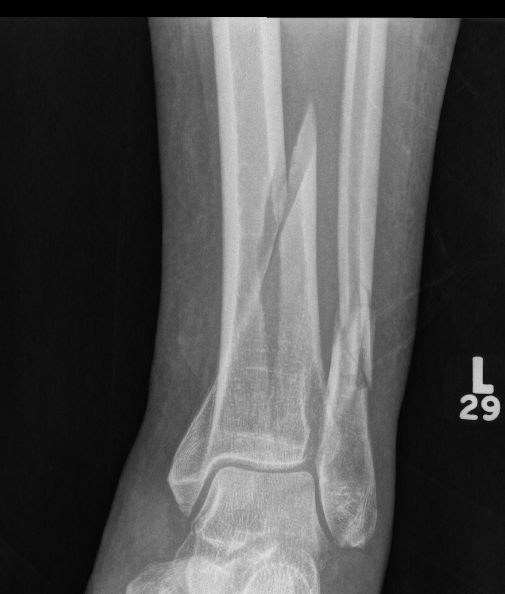

Tibial Plafond Pre External Fixator APTibial Plafond Pre External Fixator LateralTibial Plafond Post External Fixator APTibial Plafond Post External Fixator Lateral

Severe Tibial PlafondAnterolateral fragment and valgus injuryTibial Plafond External Fixator